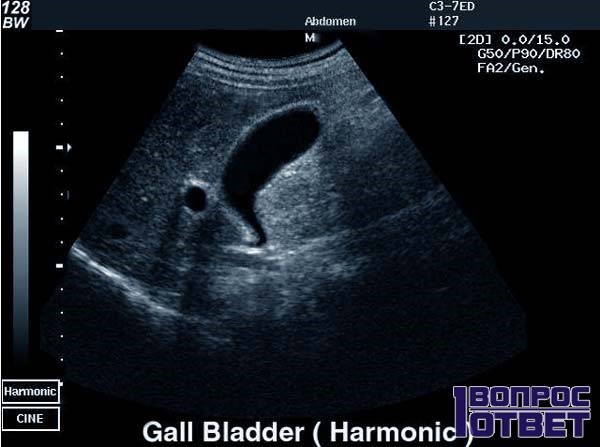

| Диагностика | УЗИ органов брюшной полости (основной метод), холецистография, МРТ, КТ, биохимический анализ крови (печеночные пробы). | УЗИ позволяет визуализировать форму желчного пузыря и оценить его функцию. |

Симптомы и диагностика: Многие люди с деформацией желчного пузыря могут не испытывать никаких симптомов, что делает диагностику сложной. Однако, если деформация приводит к застою желчи, это может вызвать такие симптомы, как боль в правом подреберье, тошнота и расстройства пищеварения. Ультразвуковое исследование является основным методом диагностики, позволяющим визуализировать изменения в форме и размере органа.

Ультразвуковое исследование является наиболее надежным методом для оценки состояния внутренних органов, включая желчный пузырь.

При обследовании желчного пузыря внимание уделяется его расположению, контурам, наличию наростов, а также характеру сокращений и другим аспектам. Здоровый желчный пузырь обычно находится на периферии правой доли печени. Его форма может варьироваться от круглой до овальной, с четкими очертаниями. Длина органа составляет от 7 до 10 см, а ширина – от 3 до 4 см.

Увеличение толщины стенок желчного пузыря может свидетельствовать о наличии воспалительного процесса, а его форма может стать неправильной.

Об обнаружении камней можно судить по усиленному ультразвуковому сигналу, причем их расположение будет изменяться в зависимости от положения тела пациента.